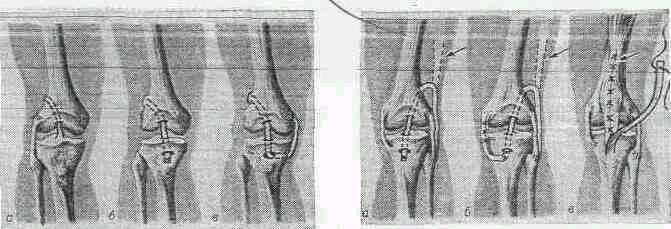

Рис 1.1. Операции на коленном суставе

Рис 1.2. Схема пластики крестообразных и боковых связок

Повреждения коленного сустава встречаются довольно часто, особенно в молодом возрасте, и могут быть следствием как прямого удара в области коленного сустава, так и приложения силы вне сустава, например при резком повороте туловища и бедра с фиксированными стопой и голенью. Могут возникать как незначительные (ущемление жировых телец, разрыв синовиальной оболочки), так и тяжелые (разрывы мениска, крестообразных и боковых связок) внутрисуставные повреждения. Как правило, все эти повреждения сопровождаются более или менее выраженным кровоизлиянием в полость сустава (гемартроз). Повреждения коленного сустава могут быть открытыми (не проникающими в полость сустава и проникающими, в том числе и огнестрельными. Закрытые часто всего возникают в результате действия прямой травмы. При непрямой травме бывает растяжения (дисторзия) или разрыв (полный или частичный) связочного аппарата. Перелом может возникать в результате как прямого, так и непрямого механизма травмы. Дифференциальная диагностика внутрисуставных повреждений коленного сустава затруднена, особенно в острый период травмы.